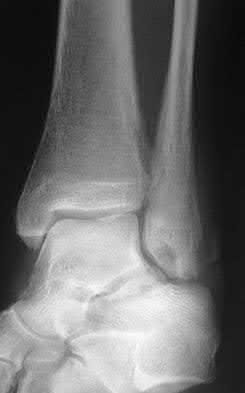

Figure A shows a patient after an open reduction and internal fixation of a bimalleolar ankle fracture.

Egol et al showed that by nine weeks, the total braking time of patients who had undergone fixation of a displaced right ankle fracture returns to the normal, baseline value.

Egol et al, also found that appropriate braking time returns at a point 6 weeks after initiation of weightbearing after treatment of lower extremity long bone and periarticular fractures, as examined with a driving simulator. No differences were seen in return of braking time between periarticular fractures and long bone injuries.